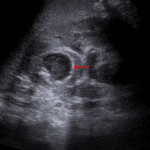

- Enlarged left kidney with diffuse loss of corticomedullary differentiation

- Hypoechoic lesion at the junction of the upper pole and interpolar region of the left kidney measuring 2.2 x 1.9 cm with a thick, echogenic rim, posterior acoustic enhancement, and no internal Doppler flow

- Mild fulness of the left renal pelvis with urothelial thickening

Pyelonephritis with renal abscess

Findings consistent with diffuse left pyelonephritis. A hypoechoic lesion at the junction of the upper pole and interpolar region of the left kidney measuring 2.2 x 1.9 cm is concerning for a renal abscess. Recommend followup ultrasound after treatment to ensure resolution of these findings and to better assess the renal parenchyma.